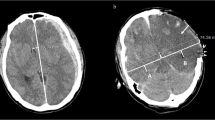

The radiologist drew a centerline from the frontal pole to the occipital pole and placed hallmarks at the quarter, halfway, and three-quarter points to divide the centerline length into 4 equal parts. The radiologist then drew lines perpendicular to the centerline to the right and left of these three hallmarks and placed regions of interest (ROIs) (10 mm [2]) along these lines at 10 mm inside the cranial bone or hematoma on either side as three measurement points of the GM and at 15 mm inside of these points as three measurement points of the WM (Fig. 1). The HU values of the WM or GM were calculated as the mean HU value of the WM and mean HU value of the GM. We also measured the displaced distance from the median (DDM), which is the difference between the centerline of the line and the centerline of the anatomical mark (Fig. 1). We assessed the correlation between outcome and HU measurements of the WM and GM or DDM.

Inter-rater reliability of the two radiologists is presented in Table 2. The kappa value (k = 0.80–0.87) indicates substantial to almost perfect inter-rater reliability. The HU values of the injury or non-injury site are indicated in Figs. 2 and 3. Only the HU value of WM in the injury site of the death group was decreased significantly. There was no significant difference in the DDM between the survival group and death group (p = 0.25) (Fig. 4). We also reanalyzed the DDM-derived hematoma thickness. The hematoma thickness was 5.2 ± 1.2 mm in the death group and 3.8 ± 2.0 mm in the survival group. There was no significant difference in the DDM subtracted hematoma thickness between the survival group and death group (p = 0.45). However, the DDM in the death group was slightly higher than that in the survival group. The DDM did not correlate with the initial FDP, SBP, or GCS. ROC analysis for HU of WM of the injury site is shown in Fig. 5. A cut-off value of 31.5 for HU of WM showed 80.0 % sensitivity and 99.9 % specificity for death; the AUC was 0.91. Of the 24 surviving patients, however, only two had a HU value of less than 31.5.

Interestingly, traumatic brain injury caused an increase in the water content of the WM. WM edema has been observed and previously reported in relation to several diseases [16]. In post-cardiac arrest patients with brain edema, the HU values of WM showed no relative change in the hypoxic group, but the HU values decreased in the GM [17–20]. Changes in HU values depend on the water content of the brain tissue. There is more water content in the GM than in the WM following a hypoxic insult to the brain that results in edema, and such edema is more often present in the cerebral cortex than in the WM [16]. In brain cell death, the fatty myelin does not change during the acute phase; however, the intra- and extracellular water content does change after cell death. The results of the present study are controversial in terms of the changes caused by traumatic brain injury. Our finding that HU values on head CT scans decreased in the WM at the injury site within a very short time following traumatic insult was interesting. The midline shift was greater than the thickness of the hematoma, meaning that the brain swelling was related to brain damage. Bartels reported that in patients with a traumatic acute subdural hematoma a clear correlation between midline shift and thickness of the hematoma was found [21]. All patients with midline shift exceeding the thickness of the hematoma by 3 mm or more died. This report supported our results of the brain swelling was related to brain damage.